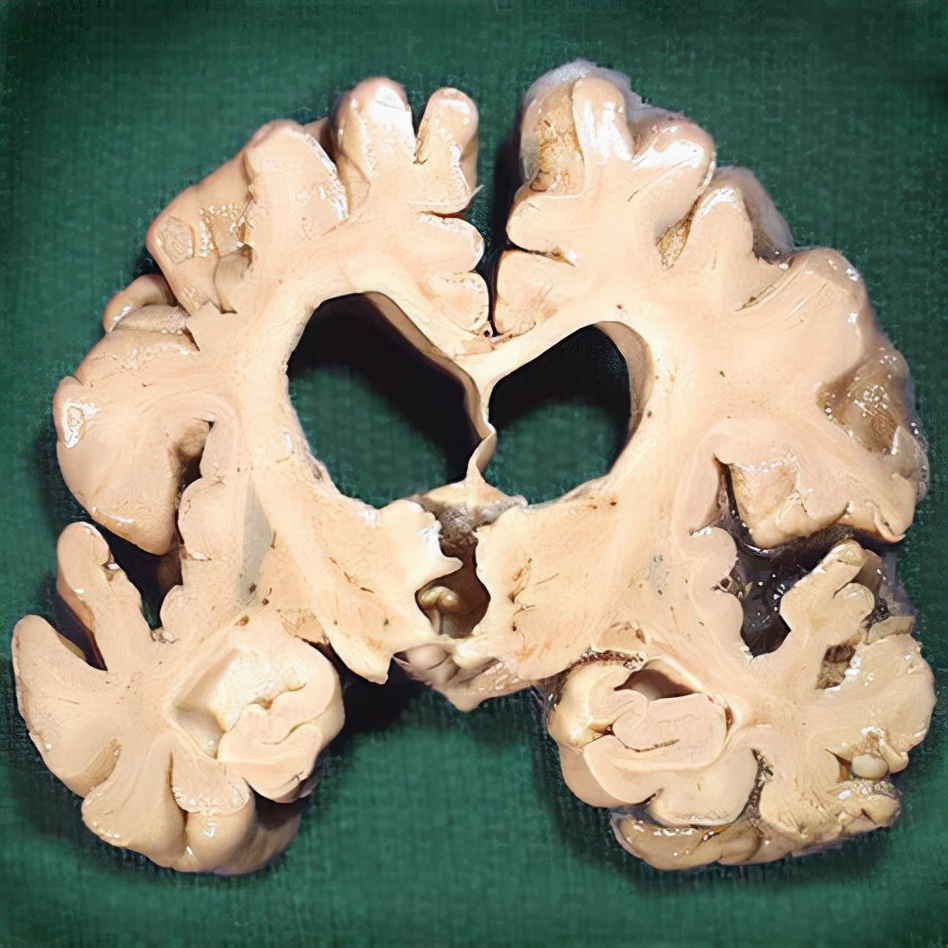

三、生理性脑萎缩。

很多人一看脑萎缩出现了,就害怕了,难道就是奔着老年痴呆去吗?

先别着急,脑萎缩可并不一定都是严重的问题,很有可能是生理性的,换句话说就是正常现象。

你能抵抗衰老吗?能永葆青春吗?答案是否定的。

人势必要衰老,身体上的每一个器官和组织都会面临衰老,大脑也不例外。

大脑的衰老方式其实有很多,其中重要的一点,就是可以明显发现大脑萎缩。

在脑CT,或者颅脑核磁共振中可以看到,脑组织一点一点变小,这种萎缩通常都是比较正常的现象。

而且即使出现脑萎缩,很多人并没有什么感觉,也没有什么症状,仅仅是在体检中发现而已,对于这种情况并不需要太过担心,这是非常正常的现象。

可是,如果是阿尔兹海默症患者就该值得关注了,具体的治疗还是应该重视医生的建议。